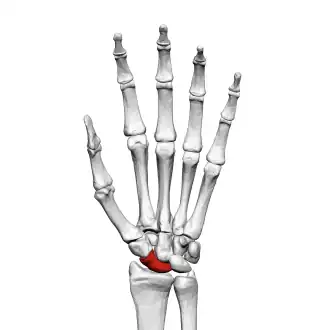

![]() Left hand anterior view (palmar view). Scaphoid bone shown in red. | |

The scaphoid bone is one of the carpal bones of the wrist. It is situated between the hand and forearm on the thumb side of the wrist (also called the lateral or radial side). It forms the radial border of the carpal tunnel. The scaphoid bone is the largest bone of the proximal row of wrist bones, its long axis being from above downward, lateralward, and forward. It is approximately the size and shape of a medium cashew nut.

The scaphoid is situated between the proximal and distal rows of carpal bones. It is located on the radial side of the wrist,[1]: 176 adjacent to the styloid process of the radius.[2] It articulates with the radius, lunate, trapezoid, trapezium, and capitate.[1]: 176 Over 80% of the bone is covered in articular cartilage.[3]